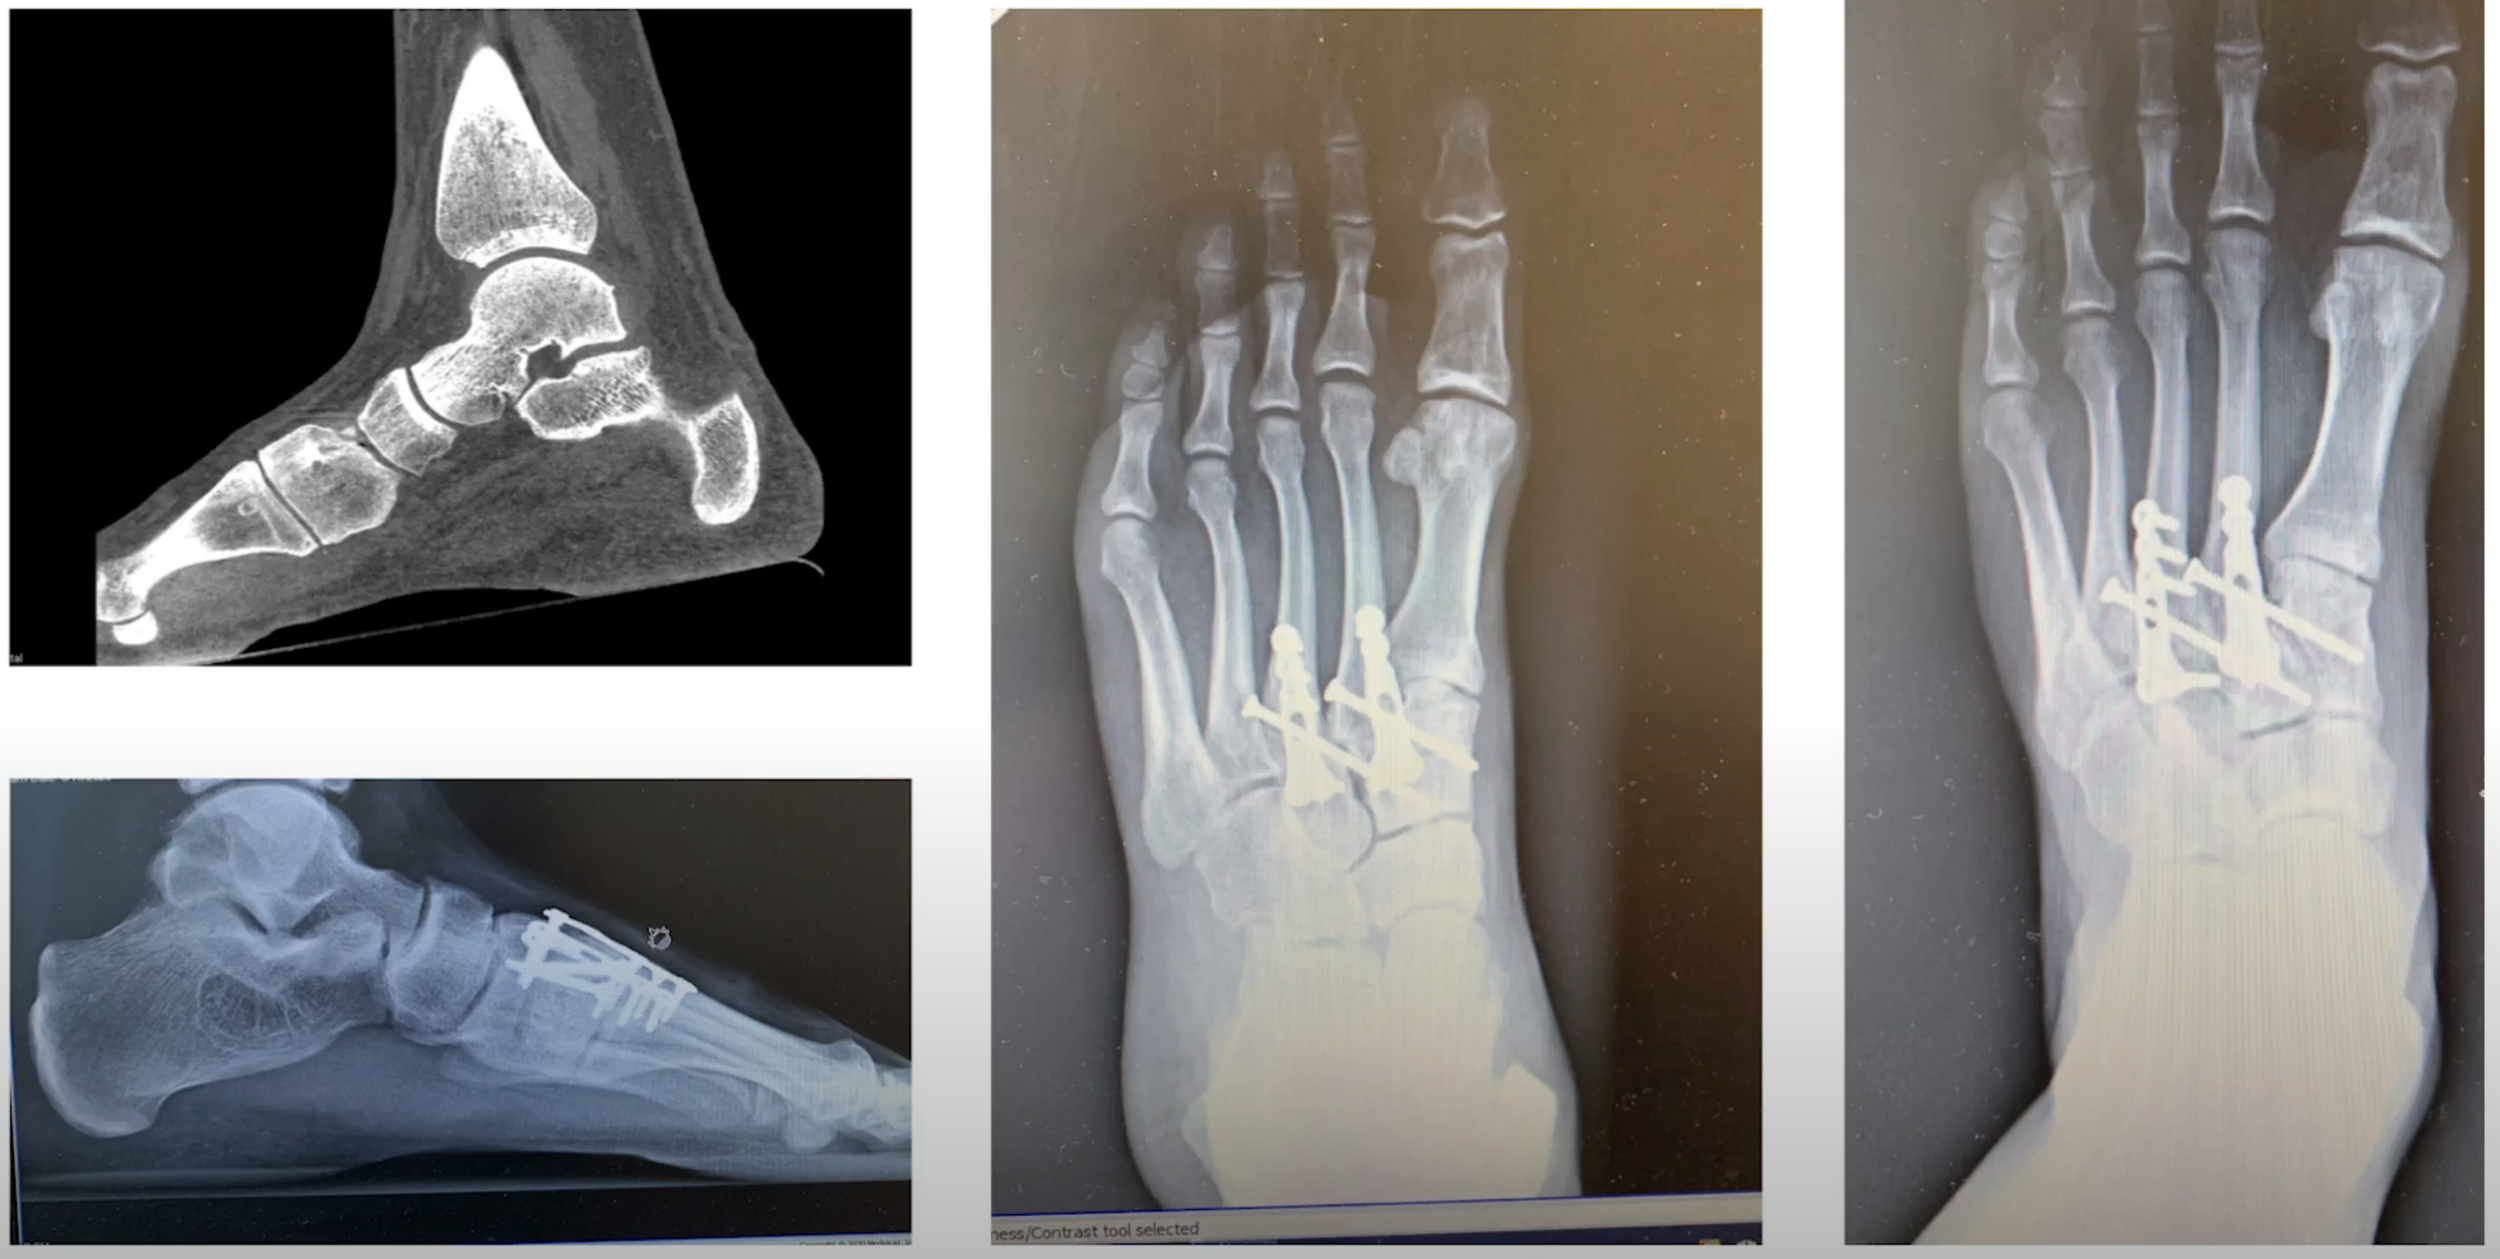

Homolateral Lisfranc in a College Quarterback

Presented at American Orthopaedic Foot & Ankle Society Conference